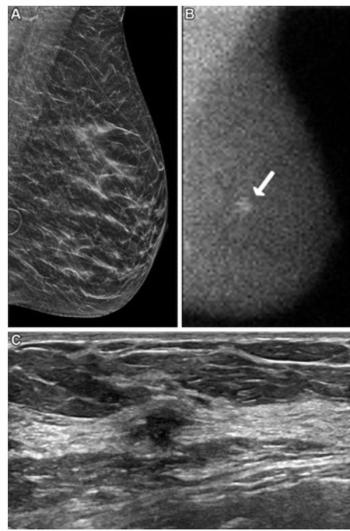

The combination of digital breast tomosynthesis (DBT) and molecular breast imaging (MBI) offered more than double the detection of invasive breast cancer with DBT in the first year of screening, according to a prospective study of nearly 3,000 women with dense breasts.

A model combining deep learning features and clinical variables demonstrated a 30 percent higher AUC than a clinical model for detecting DCIS and invasive ductal carcinoma from suspicious microcalcifications on mammography, according to a new study.